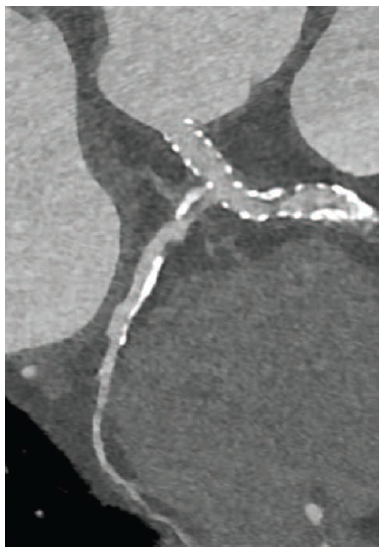

The high level of spatial resolution in a diagnostic cardiac computed tomography angiography (CCTA) scan conducted using photon-counting CT can help clinicians determine whether a patient with cardiac disease also requires an invasive coronary angiography procedure. In this case, a 5’6”, 180 lb male patient with coronary artery disease was scanned on a photon-counting CT scanner (the NAEOTOM Alpha, Siemens Healthineers) for follow-up care after stenting and evaluation for in-stent restenosis. The CT scan, which used a sequential Quantum HD Cardiac CCTA acquisition and was reconstructed in the Best Diastolic phase utilizing a 1024x1024 matrix, was performed at 140 kVp with an estimated patient radiation dose of 4 mSv. The scan revealed not only multiple areas of in-stent restenosis (Figures 1-2), but also soft and hard plaque in non-stented areas (Figures 1-3).

LAD.